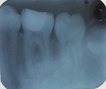

Diagnóstico: Necrosis pulpar con reabsorción radicular externa en pieza 4.7.

Tratamiento: Se realizó tratamiento de conductos en la pieza 4.7. El tratamiento se llevó a cabo en dos citas. En la primera cita se tomó longitud de trabajo y se instrumentaron los conductos con el protocolo de irrigación y se colocó hidróxido de calcio, debido a la necrosis. En la segunda cita se realizó la conometría y se obturaron los conductos con Ah Plus y técnica de obturación lateral.

Resultados: Se dieron dos citas de control y la pieza tuvo un pronóstico favorable, la lesión apical cicatrizó.